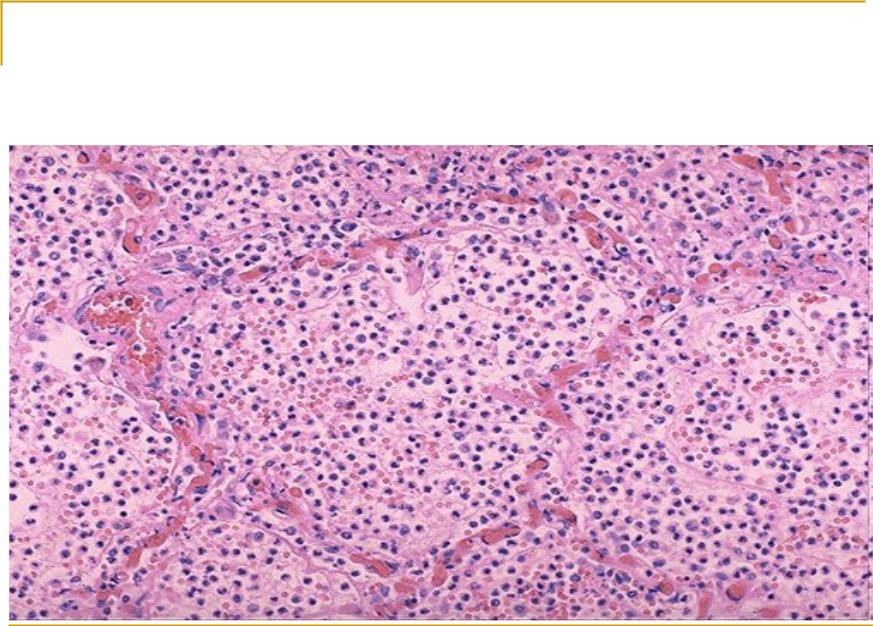

Карнификация Легкого: Микропрепараты и Диагностика

Раздел: Калейдоскоп образов